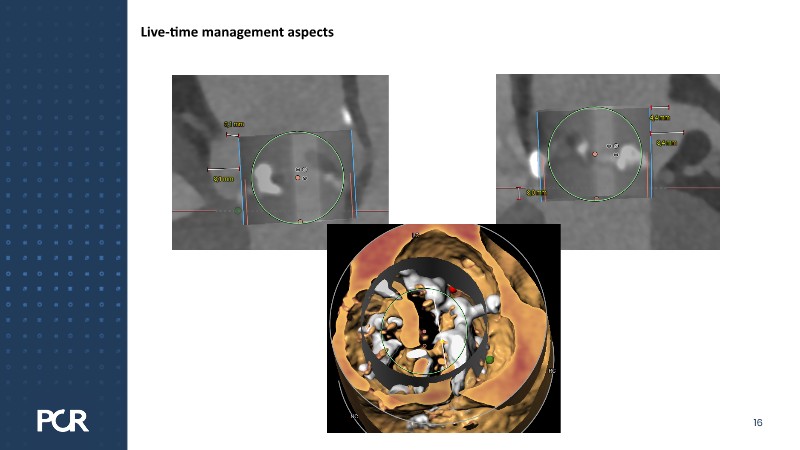

This session examines these crucial aspects through the case of a 77-year-old male with bicuspid aortic valve stenosis, HFpEF and multiple comorbidities, including diabetes, obesity and sleep apnoea.

- To understand why the planning for THV in THV is crucial for every TAVI patient at the time of the first TAVI implantation